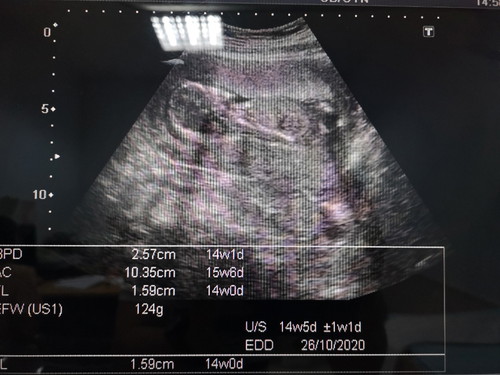

ภาวะน้ำคร่ำน้อย

อายุครรภ์ 15 weeks หมอบอกว่าน้ำคร่ำน้อย น้องไม่ค่อยมีพื้นที่ขยับตัว แม่ๆ ท่านไหนมีภาวะน้ำคร่ำน้อยบ้างมั้ยคะ ช่วยแชร์ประสบการณ์การดูและตัวเองให้หน่อยนะคะ